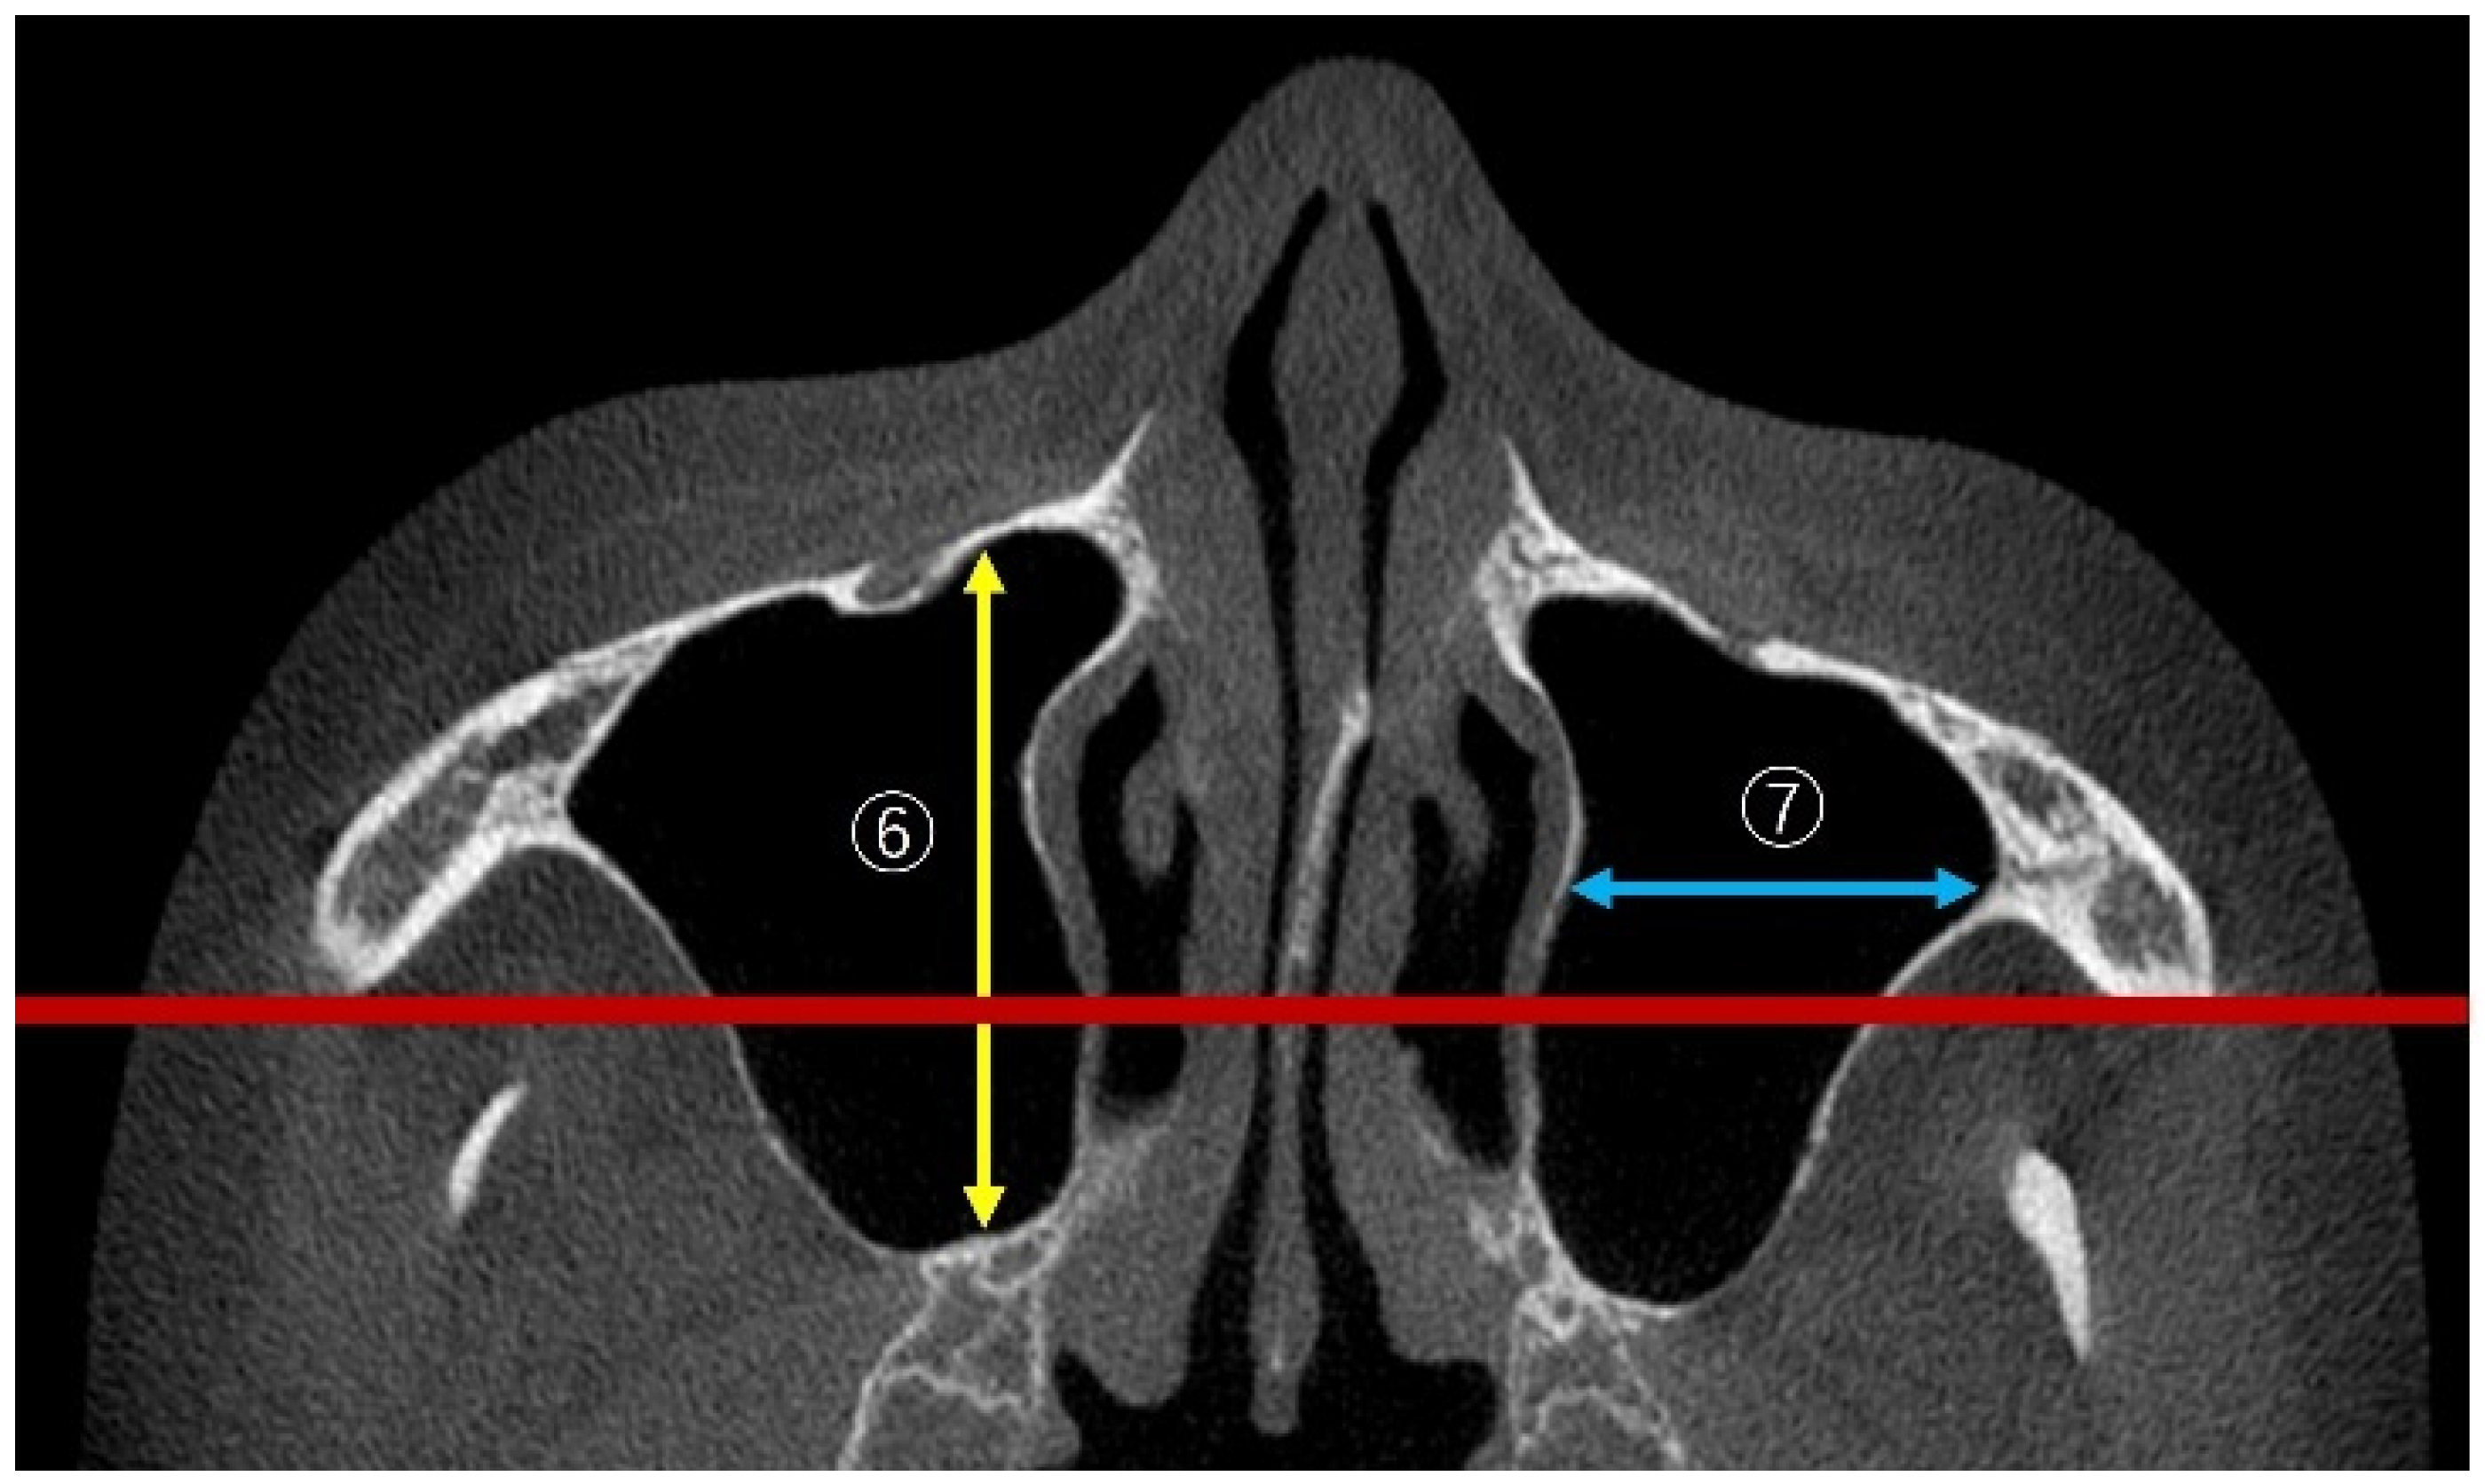

2.3.1. Linear Measurements of Maxillary Sinus Height

2.3.2. Measurement of PNR Angle and Maxillary Sinus Angle (MSA)

2.3.4. Linear Measurements of Maxillary Sinus Length